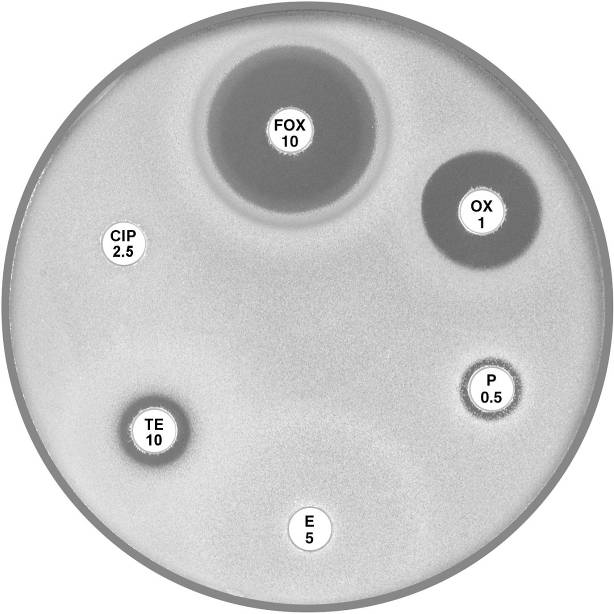

Plate 12.3.A Staphylococcus aureus ATCC 9144 (NCTC 6571) This organism is fully susceptible and has large inhibitory zones around penicillin (P 0.5), cefoxitin (FOX 10), vancomycin (VA 5) and teicoplanin (TEC 15); 12 mm, 10 mm, 3 mm and 5 mm respectively. |

Plate 12.3.B Staphylococcus aureus with low β-lactamase activity The reduced inhibitory zone around penicillin (P 0.5) with an annular radius of 4 to 5 mm indicates resistance to penicillin. The sharp edge of the inhibitory zone confirms β-lactamase production. |